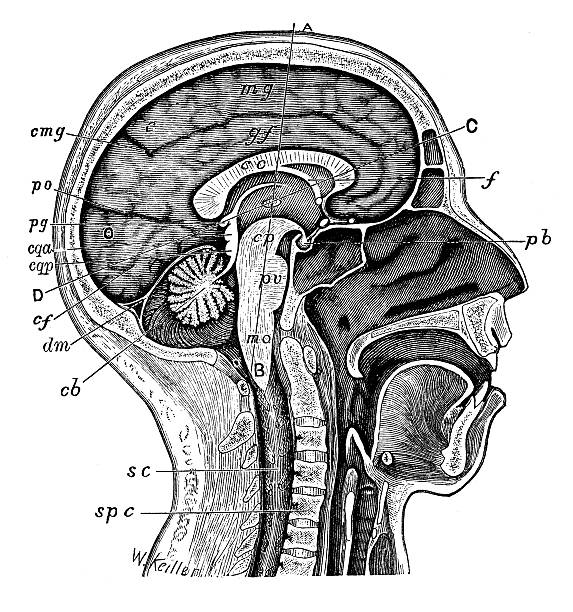

인후두 역류 질환은 위산이 인후두까지 역류하여 염증을 일으키는 질환입니다. 이 질환은 식도역류와 비슷한 증상을 보이며, 특히 목이 간질간질하고 마른 기침이 나타날 수 있습니다. 인후두 역류 질환 환자는 목의 염증과 마찰로 인해 간질감이 생겨, 기침을 할 때 목이 간질하고 마르게 느껴지는 것입니다.

또한 인후두 역류 질환은 트라우마나 중성지방, 당뇨, 흡연, 알코올 등 다양한 요인에 의해 발생할 수 있으며, 식습관 개선과 약물 치료를 통해 증상을 완화시킬 수 있습니다. 인후두 역류 질환은 만성적으로 발생하면 위암 등의 합병증을 유발할 수 있으므로, 조기에 의학적인 상담과 치료가 필요합니다. 증상이 나타날 경우 의료진의 상담을 받아 적절한 검사를 시행하고, 증상의 원인을 파악하여 적절한 치료 방법을 선택하는 것이 중요합니다.